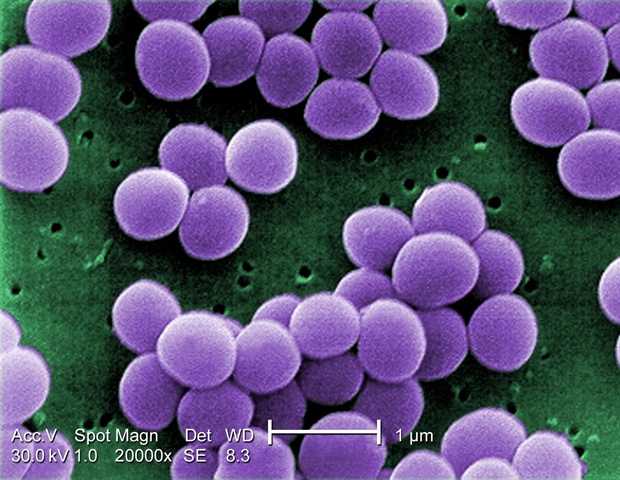

הכריזה על פרסום מאמר חדש עבור זונוזות כְּתַב הָעֵת. עמיד במתיצילין Staphylococcus aureus (MRSA) ועמידות בפני וונקומיצין Staphylococcus aureus (VRSA)